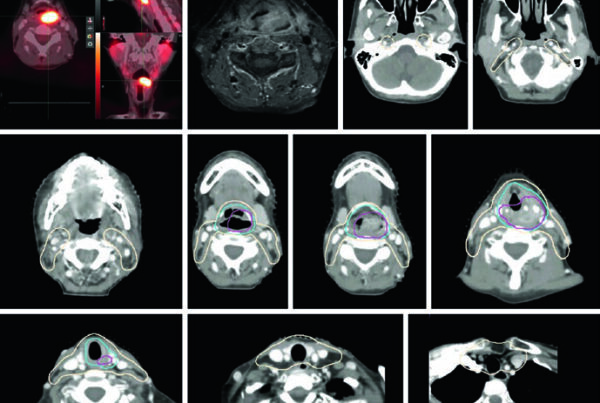

Comparação entre Algoritmos na Prática Clínica

A diferença entre algoritmos se manifesta mais claramente em condições desafiadoras: campos pequenos, feixes de alta energia e heterogeneidades acentuadas — especialmente pulmão. A figura ao lado ilustra isso de forma dramática: para um feixe de 15 MV, campo 2,8×14 cm, 4 cm off-axis, atravessando 10 cm de pulmão (ρ = 0,2 g/cm³), as curvas de dose em profundidade divergem significativamente entre os algoritmos.

Monte Carlo ($MC_w$) serve como referência. O Collapsed Cone (CC-TMS, CC-PIN) acompanha razoavelmente bem, com desvios moderados na interface e dentro do pulmão. O AAA (AAA-ECL) segue de perto o CCC mas com desvios na interface tecido-pulmão. Já o Pencil Beam (PB-TMS, PBC-ECL) superestima a dose dentro do pulmão por uma margem clinicamente significativa e não consegue reproduzir a redução de dose lateral causada pela falta de equilíbrio eletrônico.

Na prática clínica, a escolha do algoritmo deve considerar o sítio anatômico e o cenário clínico. Para planejamentos em abdome, pelve ou cabeça e pescoço — onde as heterogeneidades são menos dramáticas — mesmo um pencil beam pode ser aceitável para planejamento forward, embora um algoritmo tipo “b” seja sempre preferível. Para pulmão, mama com campo tangencial passando por pulmão, mediastino, ou qualquer situação com campos pequenos de alta energia, um algoritmo tipo “b” (CCC, AAA, Monte Carlo ou Acuros) é essencial e não-negociável.